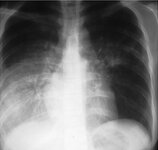

Pulmonary tuberculosis

Pulmonary TB with cavitation

From the personal collection of David Horne and Masahiro Narita; used with permission